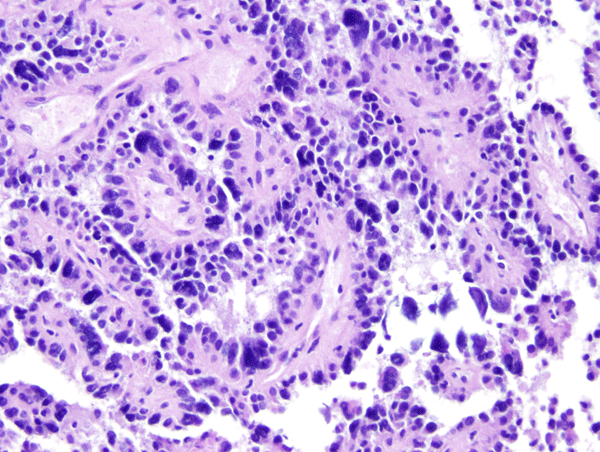

Choroid plexus tumors affect mostly children and young adults. They are a continuum which includes choroid plexus papilloma-CPP (WHO grade I), atypical CPP (WHO grade II) and choroid plexus carcinoma-CPC (WHO grade III). CPC is most common in very young children and is seen in older patients. In children, CPP and CPC arise in both, lateral and fourth ventricles. In adults, CPP is more frequent in the fourth ventricle and sometimes arises in the cerebellopontine angle. CPP is seen in the Aicardi syndrome, an X-linked syndrome in females, characterized by agenesis of the corpus callosum, chorioretinal lacunae, and infantile spasms. CPC occurs in the rhabdoid tumor predisposition syndrome, caused by germline mutations of the INI1 gene. Choroid plexus tumors cause hydrocephalus and increased intracranial pressure by blocking CSF pathways and by oversecreting CSF. CPC can also seed the subarachnoid space. Both, CPP and CPC have a papillary basic structure. In CPP the papillae are covered by a single layer of benign epithelial cells, similar to normal choroid plexus. In CPC the tumor cells are multilayered, atypical, and mitotic, and the papillary structure may be effaced such that the tumor appears solid.